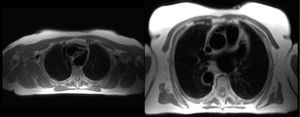

Mujer de 69 años, con síncopes y reciente diagnóstico de miocardiopatía hipertrófica, fue remitida a nuestra unidad de imagen para completar estudio con resonancia magnética cardiaca. Esta confirmó la miocardiopatía hipertrófica (septo mediobasal de 17 mm) con obstrucción al tracto de salida del ventrículo izquierdo y movimiento sistólico anterior de la válvula mitral (figura 1). En los cortes axiales anatómicos, se observó una imagen compatible con doble arco aórtico (figura 2), que se confirmó con la realización de aortografía con contraste y posterior reconstrucción tridimensional. Las imágenes tridimensionales (figura 3) mostraron un doble arco aórtico completo con origen de subclavia y carótida derechas en el arco derecho y de carótida y subclavia izquierdas en el izquierdo. La paciente negó tener síntomas que pudiesen estar en relación con este hallazgo (disfagia, estridor o disnea).

El doble arco aórtico es una anomalía que tiene una incidencia en torno al 1-2% de todas las enfermedades congénitas de corazón y aorta. Se trata de un anillo vascular completo, caracterizado por la presencia de los arcos aórticos izquierdo y derecho conectados, englobando la tráquea y el esófago. Usualmente se diagnostican en la infancia, y la corrección quirúrgica tiene buen pronóstico. Esporádicamente se han reportado casos en la edad adulta, y el motivo más frecuente de consulta es disfagia y síntomas similares al asma. Casos de pacientes añosos y asintomáticos como el nuestro son excepcionales.